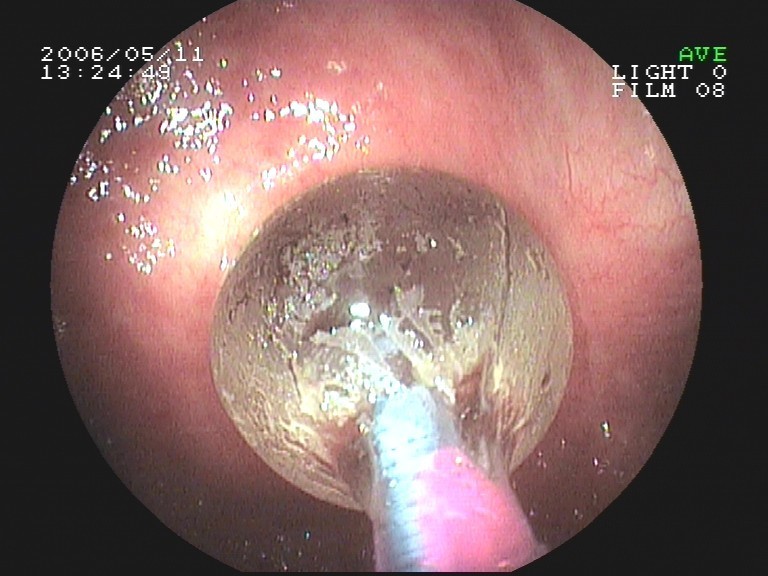

Coloskopie - riesiger rasenförmiger Polyp, Abtragungsstelle n. kompl. Abtragung (mit Stromschlinge)